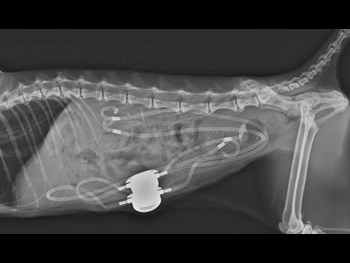

人工尿管(SUBシステム2.0)を設置

尿管結石を取り除き人工尿管(SUBシステム2.0)を設置しました。

水腎症は改善しました。

結石も取り除きの痛みからも解放されて元気に退院してくれました。

新しいSUBシステム2.0を設置

漏れている左尿管を修復しSUBシステム2.0を左右の腎臓に装着しました。

SUBシステムを設置しました。

漏れを確認して終了となりました。